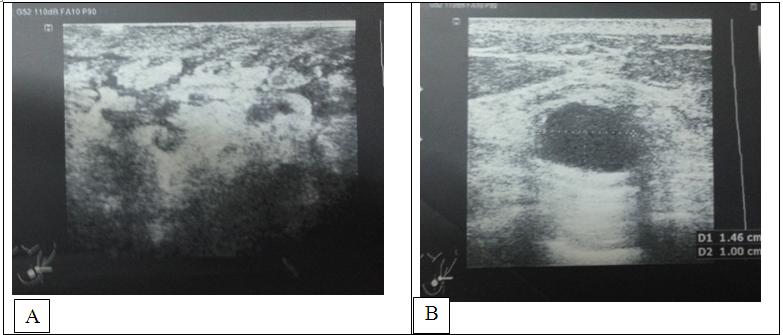

-         Bệnh nhân được chụp PET/CT đánh giá giai đoạn:

• Chiếm toàn bộ vú phải là khối u kích thước17x15x19cm, xâm lấn phần mềm, xương, da thành ngực, tăng hấp thu18F-FDG, max SUV=10,42

• Nhiều hạch nách phải, hạch lớn nhất kích thước 25x36mm maxSUV=6,22

• Nhiều hạch nách trái, hạch lớn nhất kích thước12x22mm, max SUV=5,26

• Hạch trung thất trước trên kích thước 25x25mm, max SUV=10,35

• Thùy trên phổi trái có nốt mờ kích thước 1cm, không tăng hấp thu 18F-FDG

• Dịch màng phổi phải dày 3,4cm

• Tổn thương cung trước xương sườn 4,5 phải maxSUV=5,3

Hình 3: Hình ảnh chụp PET/CT trước điều trị